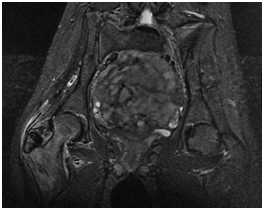

The patient progressed satisfactorily. The symptoms had disappeared 2 months after the procedure (Figure 4).

Figure 4 Simple x-ray two months after the treatment.